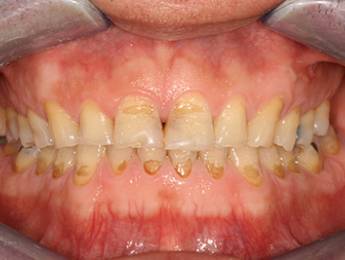

Nagymértékű fogkopás, erózió, csikorgatás a teljes rágóapparátust túlterhelve okoz reménytelennek tűnő helyzeteket.

Ebben az esetben implantátumok , koronák és hidak segítségével változtattunk a páciens fogainak érintkezésén. 6 hónapig ideiglenes hidakkal teszteltük a megváltoztatott harapási pozíciót. Ezután készültek el a végleges fix pótlások.